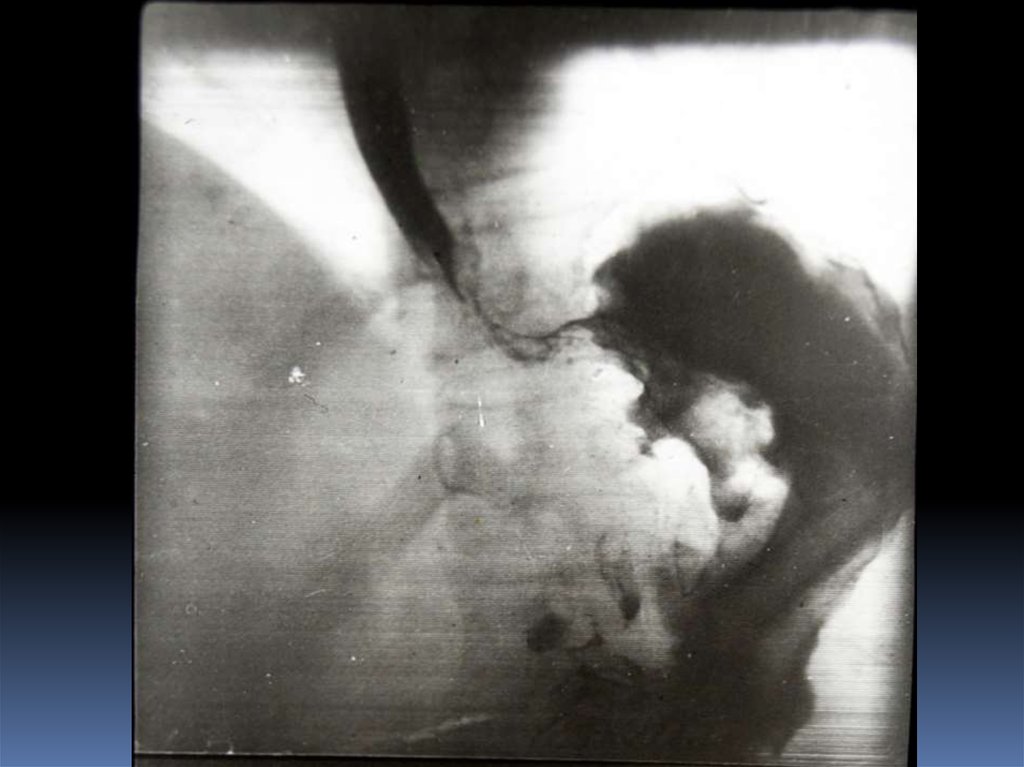

16. Рентгенодиагностика рака желудочно-кишечного тракта

Рентгенодиагностика

рака желудочнокишечного тракта

17. Классификация рака органов ЖКТ

1. Экзофитная форма:

2. Эндофитная форма:

узловая форма;

диффузноинфильтративная

форма;

полипоподобная

чашеподобная форма. инфильтративноязвенная.

3. СМЕШАННАЯ ФОРМА – 10-15%